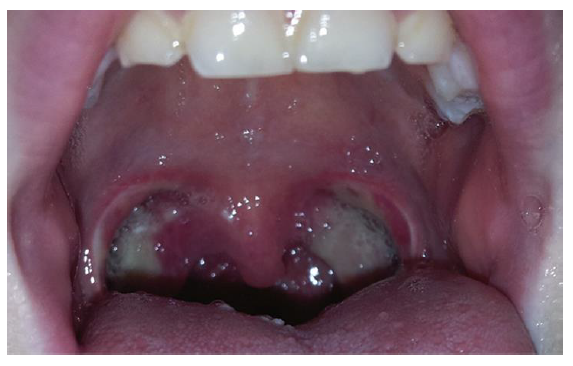

Typical post-operative appearance on day 10.